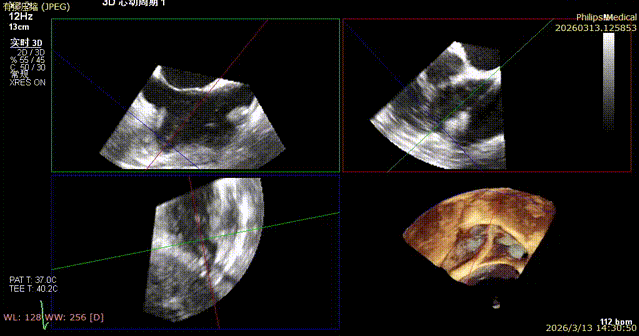

1. The first 14T device was positioned under the mid-esophageal bicaval view on TEE, and the tip of the delivery catheter was observed to point to the posterior-septal commissure of the tricuspid valve using 3D mode.

2. Under 3D mode switched to MPR-MultiVue mode, the trajectory was adjusted to anchor the tricuspid annulus.

3. The pull test was completed under MultiVue mode.

4. After opening the clipping component, the orientation was adjusted under 3D mode.

5. Apposition to the tricuspid annulus under 3D mode.

6. Under the guidance of MultiVue mode and DSA, the anchoring pull rod was retracted and the clipping component was closed to complete the clip application.